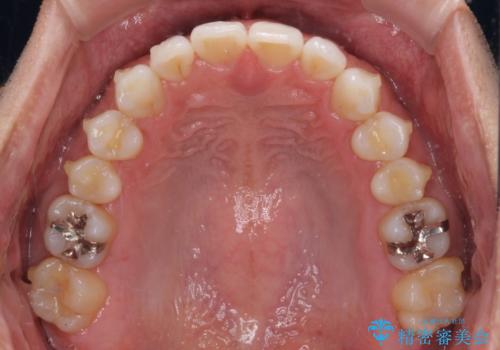

- 上下前歯のデコボコを気にして来院された患者様です。

以前矯正をした後戻りということで、歯列不正はそれほど大きくなかったため、インビザライン・ライトを用いて矯正治療を行うこととしました。

1日22時間以上しっかりと装着してくださったので、半年かからずに治療を終えることができました。